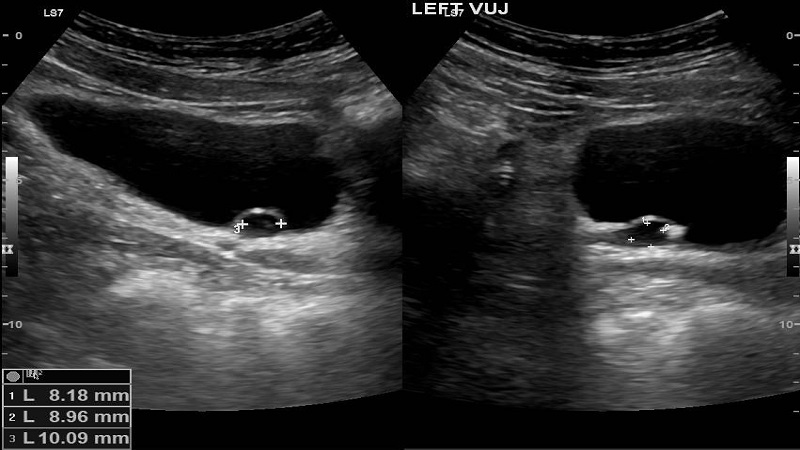

Để chẩn đoán bệnh lý này, bác sĩ thường áp dụng các phương pháp sau:

Đặc biệt thông qua việc siêu âm thai và các phương thức sàng lọc dị tật, bệnh lý trên có thể được chẩn đoán sớm ngay từ khi trẻ chưa chào đời (dị tật bẩm sinh).